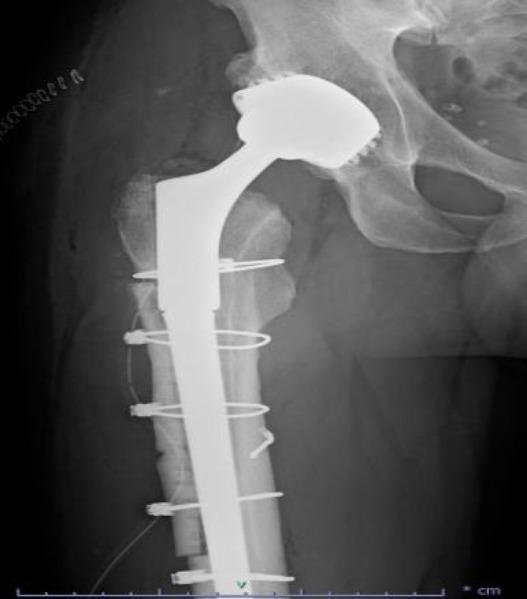

模块化牢固固定型髋关节翻修柄骨折:一例报告及文献综述

Modular Well-Fixed Hip Revision Stem Fracture: A Case Report and Literature Review.

This study presents a case of repeated prosthetic fractures in a modular hip prosthesis in a 56-year-old male patient. After the initial implantation of a modular total hip prosthesis in 2006, the patient experienced two instances of prosthetic implant fractures over seventeen years. In this study, we analyze the clinical case, explore potential underlying causes of this complication, and delve into current indications and strategies for the revision of fractured prosthesis stems. The discussion is informed by a literature review and underscores the significance of selecting appropriate revision techniques to address this challenge.

摘要

本研究报告了一例56岁男性患者模块化髋关节假体反复发生假体骨折的病例。2006年首次植入模块化全髋关节假体后,该患者在十七年中经历了两次假体植入物骨折。在本研究中,我们分析了该临床病例,探讨了这种并发症的潜在根本原因,并深入研究了目前骨折假体柄翻修的适应症和策略。讨论以文献综述为依据,并强调选择合适的翻修技术来应对这一挑战的重要性。